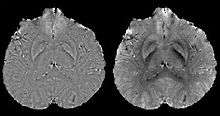

COSMOS assumes a model-free susceptibility distribution and keeps full fidelity to the measured data. This method has been validated extensively in in vitro, ex vivo and phantom experiments. Quantitative susceptibility maps obtained from in vivo human brain imaging also showed high degree of agreement with previous knowledge about brain anatomy. Three orientations are generally required for COSMOS, limiting the practicality for clinical applications. However, it may serve as a reference standard when available for calibrating other techniques.

MEDI has also been validated extensively in phantom, in vitro and ex vivo experiments. In in vivo human brain, MEDI calculated QSM showed similar results compared to COSMOS without statistically significant difference.[15] MEDI only requires a single angle acquisition, so it is a more practical solution to QSM.